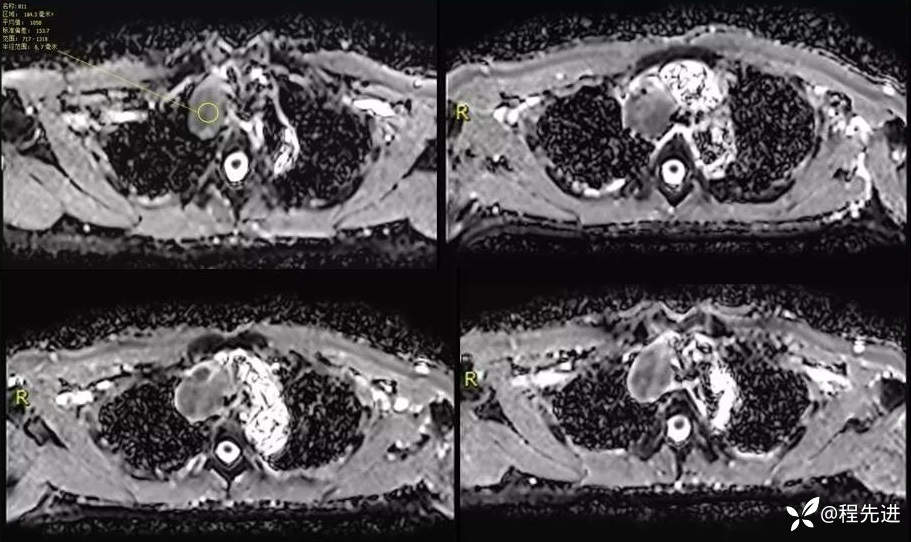

MR

T1+C 动脉增强